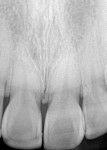

This article demonstrates the use of a soft-tissue diode laser (Odyssey® Navigator, Ivoclar Vivadent, www.ivoclarvivadent.us) in combination with a nanohybrid direct composite resin (IPS Empress Direct, Ivoclar Vivadent) to enhance the smile of a 28-year-old woman who presented with a chipped central incisor and an unbalanced excessive gingival display (Figure 1 and Figure 2). In the past, lasers would not have been considered to correct the unbalanced and excessive gingival display; only the chipped central incisor would have been addressed. However, because the patient noticed the imbalance, and the subtle soft-tissue correction could be completed in a minimally invasive way using the soft-tissue laser, the patient desired the combination of direct composite and in-office gingival treatment. She declined more aggressive treatment with indirect porcelain veneers and osseous contouring. Additionally, given the patient’s relatively young age and the overall healthy condition of her teeth, this was the most appropriate treatment plan to achieve the anticipated results.